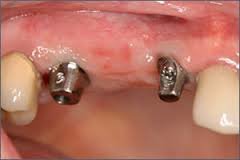

| Dental Implants | $13,999 |